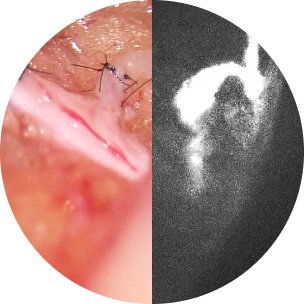

High Resolution

今までにないクリアな見え味。高倍率でも鮮明な画像を提供し、外科医が1mm 以下の血管でもストレスなく手術する事を可能にします。